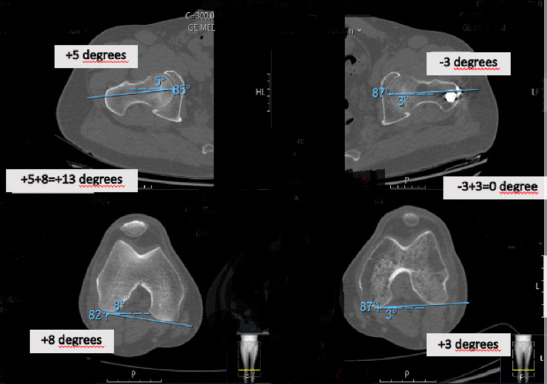

Methods: A retrospective cohort study was conducted involving 54 adults treated with closed static-locked IMN for diaphyseal femur fractures between 2014 and 2019. Rotational alignment was assessed using computed tomography (CT)-measured femoral anteversion (FAV) differences, with a threshold of ≥15° defined as malalignment. Multivariate logistic regression was employed to examine associations with fracture pattern, nail entry site, surgical timing (day vs. night), and coronal alignment. Functional outcomes were assessed using the WOMAC (Western Ontario and McMaster Universities Osteoarthritis Index) knee, Harris hip, Lower Extremity Functional Scale, and Kujala patellofemoral scores. Receiver operating characteristic (ROC) analysis was used to determine optimal FAV thresholds.

Results: Rotational malalignment (≥15° FAV difference) was observed in 33.3% of cases, with 94.4% involving internal rotation. Multivariate analysis identified no independent predictors among the following factors: fracture location (proximal 44.4% vs. middle 29.2%, p=0.625), AO classification (Type A 34.3% vs. Type C 33.3%, p=0.914), nail entry site (lateral trochanteric 40% vs. piriformis 16.6%, *p*=0.574), and surgical timing (night 26.1% vs. day 38.7%, p=0.228). Patients with malalignment demonstrated significantly poorer functional outcomes, as evidenced by higher WOMAC knee scores (12.7+-4.8 vs. 6.4+-4.8, p<0.001). ROC curve analysis identified 13.5° as the optimal FAV threshold (area under the curve, AUC: 0.78), although the 15° cutoff maintained strong clinical utility with a specificity of 83%.